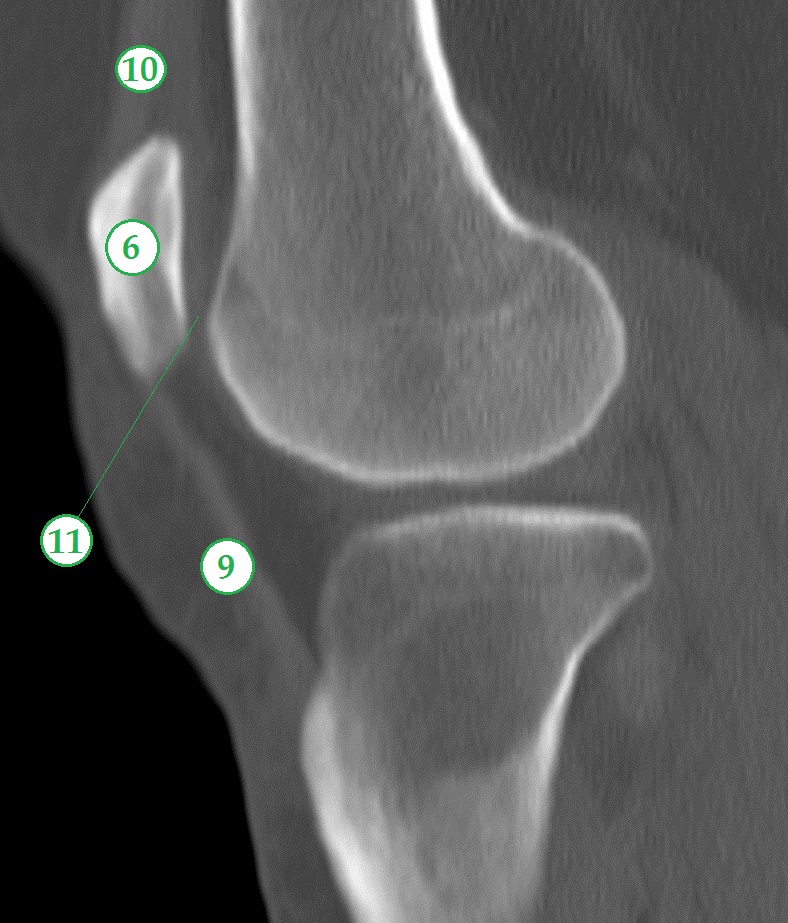

Заболевания и медицинские снимки: Жидкость в коленной чашечке

Раздел: Галерея прозрений